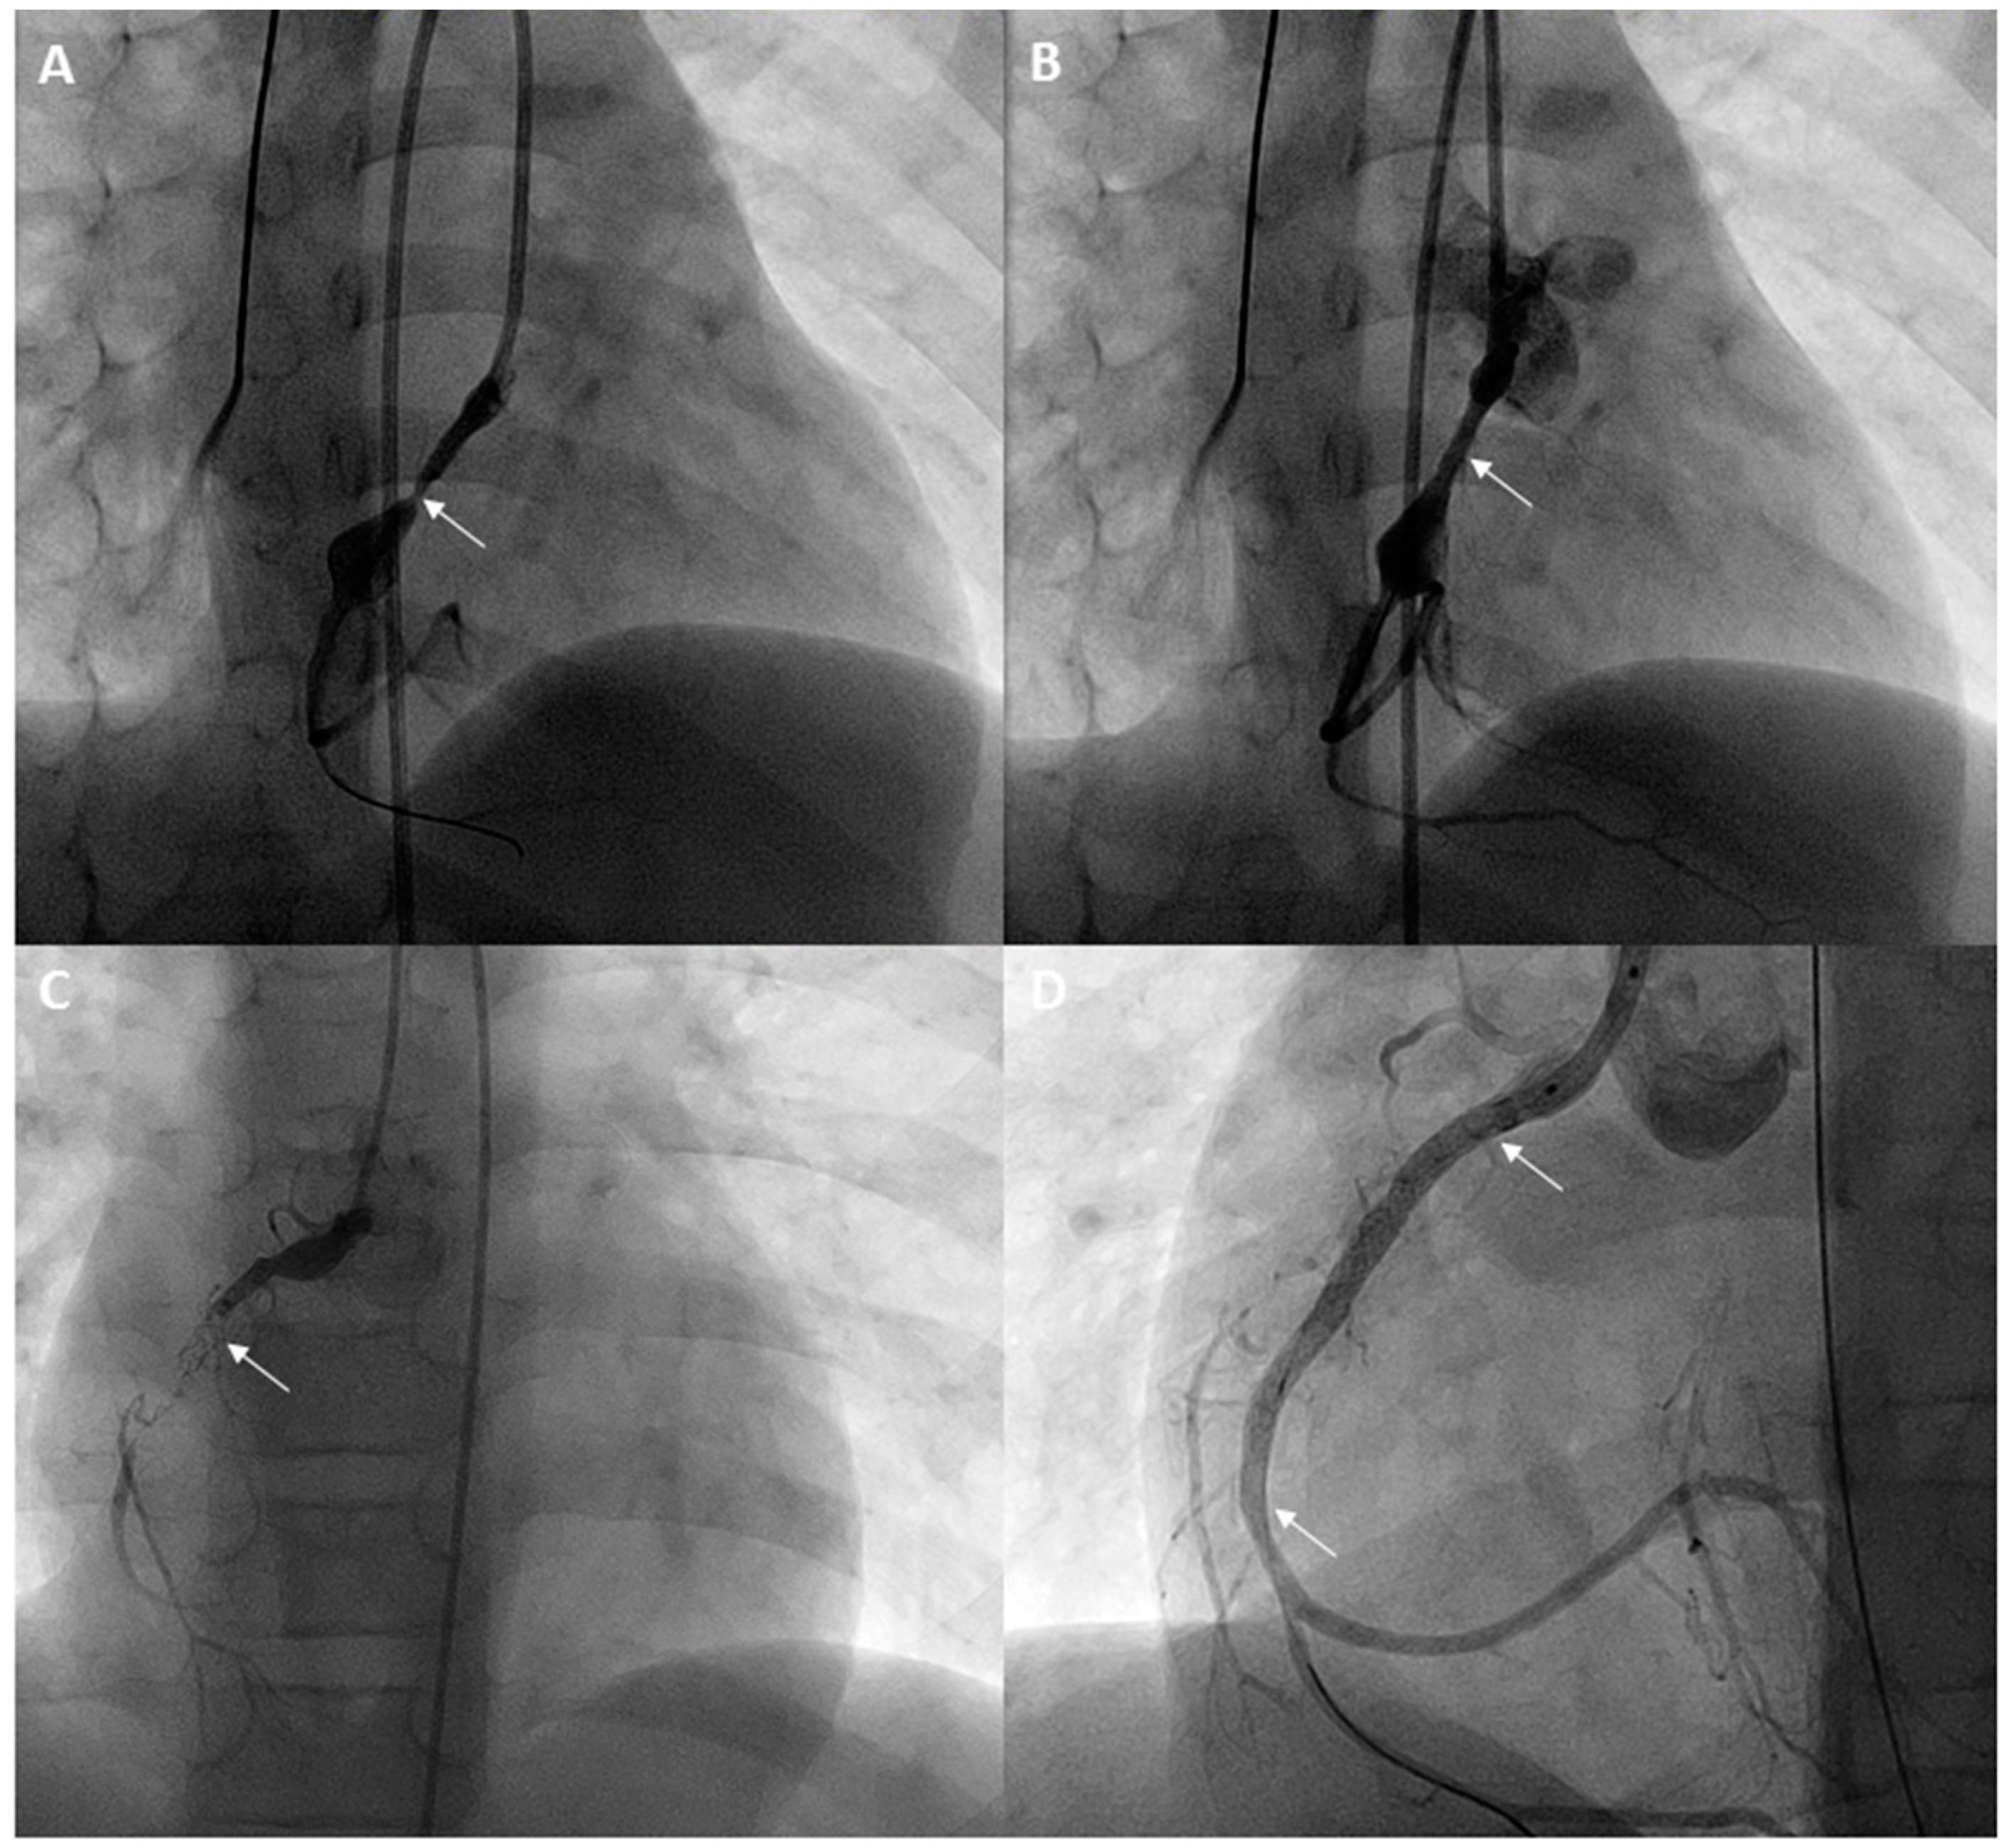

Children and adolescents with Kawasaki disease who have recurrent stenosis following angioplasty should be considered for stenting (Figure 1). Although bare metal stents have been used for this purpose in the past [18,21,22], drug eluting coronary stents should be used in this era and can generally be introduced using 5 Fr guide catheters as well. These stents have excellent patency rates and have low incidence rates of new aneurysm formation. The diameter of the stent chosen should be equal to the size of the adjacent normal vessel. The shortest length of the stent should be used and care should be taken to avoid jailing any side branches. Following the procedure, stent prophylaxis is necessary. In addition to Aspirin 5 mg/kd/day, clopidogrel 4 mg/kg loading dose is given followed by maintenance with 1mg/kg/day in children for more than 2 months [22], and preferably up to 6 months, based on extrapolation from adult data. Low molecular weight heparin or coumadin should be used if large coronary aneurysms are still present. Although there is lack of long-term data, it may be beneficial to use statins in Kawasaki disease patients with severe coronary artery disease.

Figure 1.

A 7-year-old with a history of Kawasaki disease and giant coronary artery aneurysms of the left main coronary artery and right coronary artery underwent a cardiac catheterization. Fractional flow reserve with adenosine in the right coronary artery (RCA) was 0.74. Stenosis proximal to the aneurysm in the RCA is seen (arrow) (A). After placement of a drug-eluting stent, the stenosis has resolved (arrow) (B). Two years later, a cardiac MRI showed an inducible perfusion defect in the inferior septum and inferior wall. Angiograms in the RCA showed complete occlusion of the RCA stent (arrow) (C). After recanalization and angioplasty, an overlapping stent was placed extending to the distal RCA (lower inferior arrow) (D) and an additional proximal stent was also placed (superior arrow) (D), reestablishing flow in the RCA.